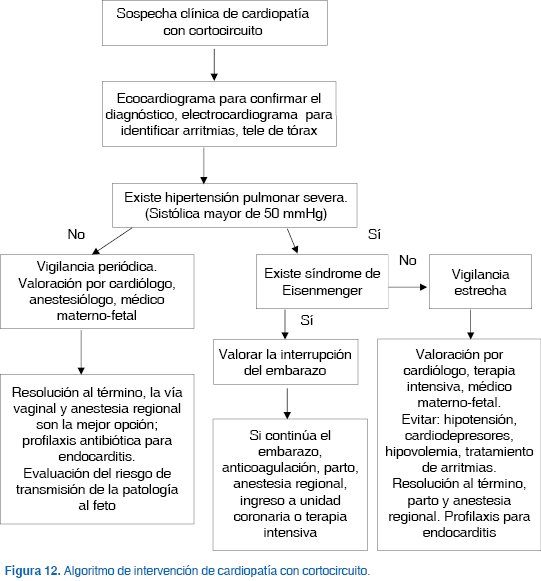

En la figura 12 se muestra el algoritmo de intervención diseñado para sospecha clínica de cardiopatía con cortocircuito durante el embarazo.